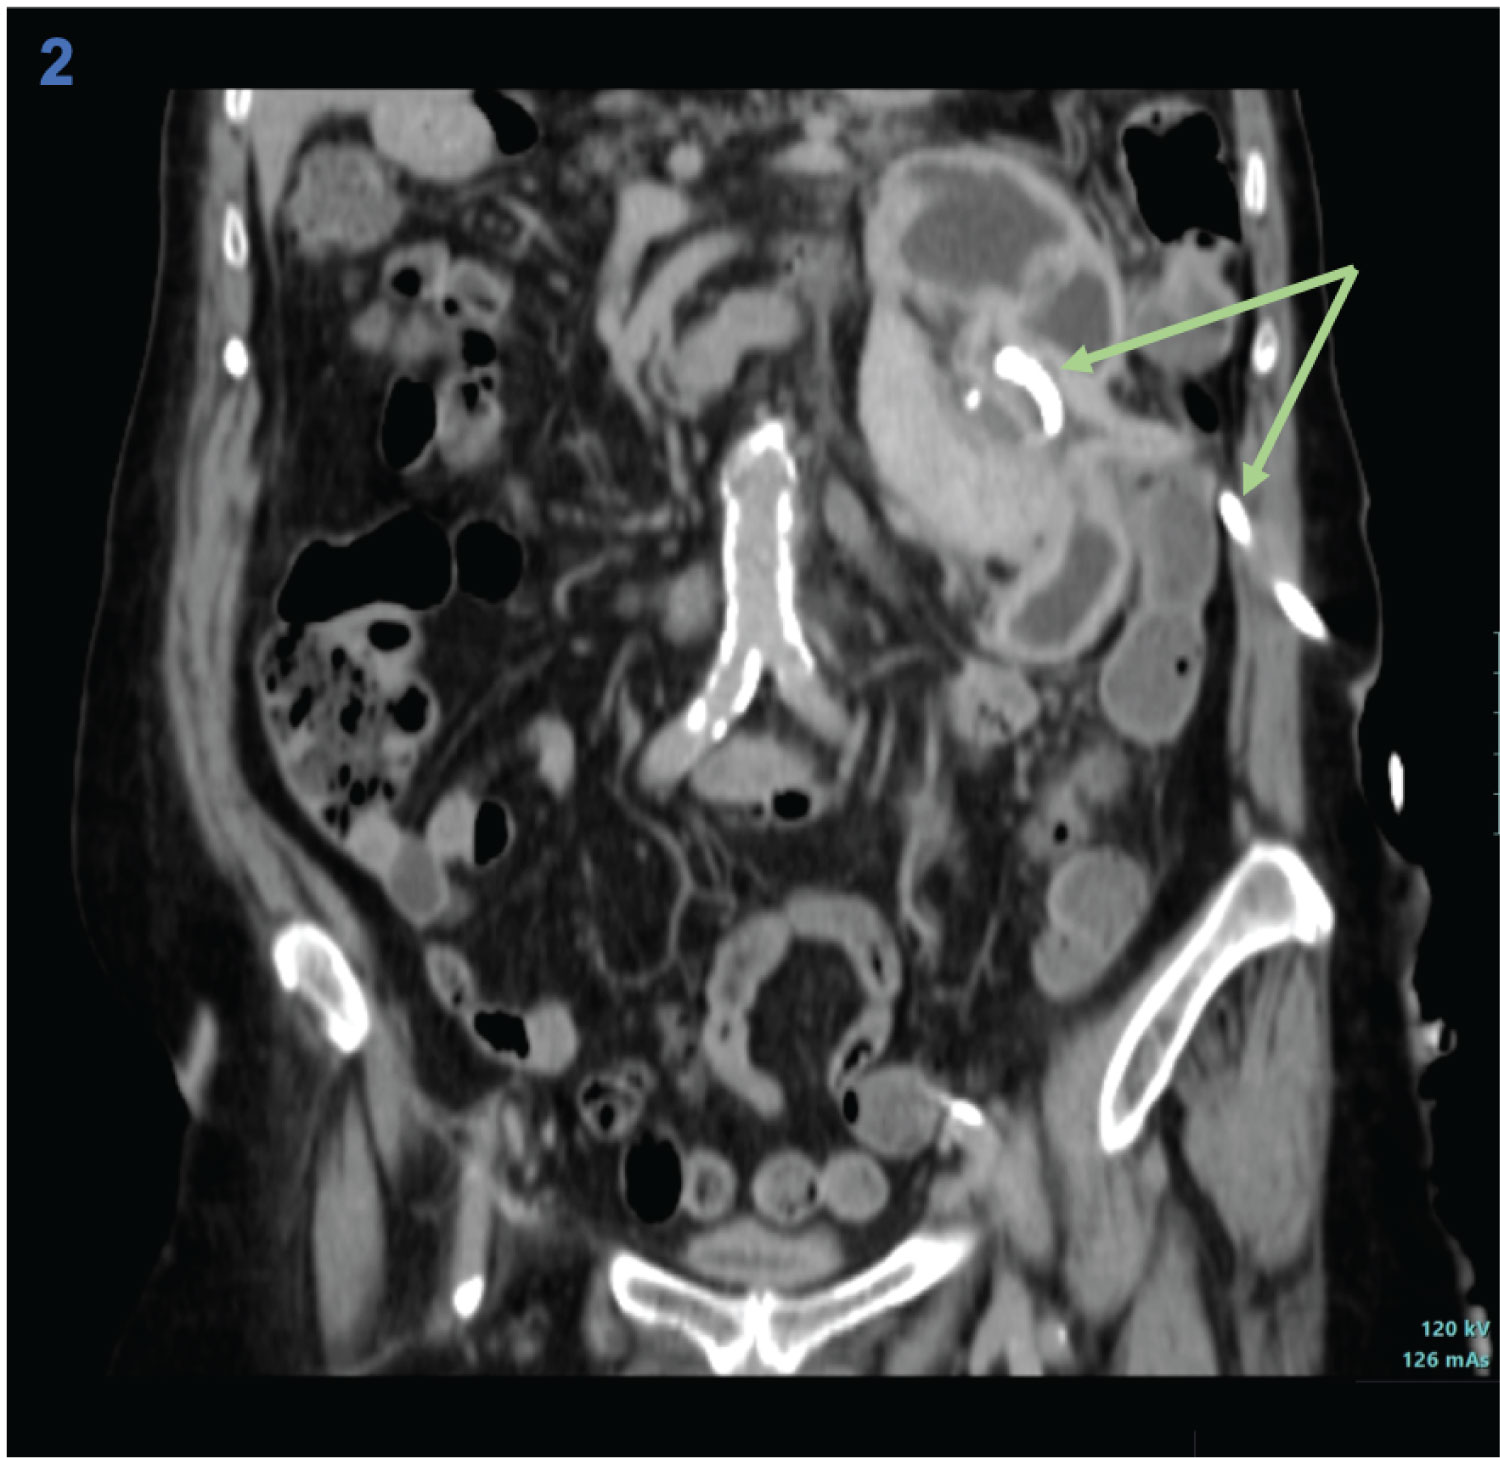

An 80-year-old woman with a history of metabolic syndrome, ischemic heart and cerebrovascular disease was admitted at the emergency department with asthenia and left abdominal and flank pain. She was on day 5th of empiric cefuroxime for urinary tract infection. On physical examination, the patient was febrile, but hemodynamically stable; an abdominal mass in the left flank was evident and painful on deep palpation; ipsilateral Murphy's sign was present. Laboratory studies showed a marked elevation of C-reactive protein (329.9 mg/L), normal renal function, and mild isolated leukocyturia (70/µL) on urinalysis. A contrast-enhanced abdominal-pelvic computed tomography scan revealed an enlarged left kidney conditioned by a multiloculated cystic lesion (14 × 11 mm in the axial plane; 21 mm in the longitudinal plane), with homogeneous content and regular parietal thickening, associated to heterogeneous densification of the left perirenal fat, without hydronephrosis (Figure 1). In the absence of unequivocal findings of complicated cyst, the diagnosis of acute pyelonephritis with failure to cephalosporin therapy (no prior urine culture) was assumed, and piperacillin/tazobactam was started. However, since the patient maintained persistent fever and elevated inflammatory markers, the possibility of occult cyst infection was considered. Thus, a percutaneous approach was performed with immediate drainage of 1500 mL of purulent content. Multisensitive K. pneumoniae and E. coli were isolated in the cystic fluid, and the antibiotic spectrum was narrowed to cefuroxime, according to the antibiogram, and drainage of the cyst was maintained through a pigtail drain (Figure 2). She evolved favorably, having completed 1 month of antibiotic and subsequently referred to Urology consultation for a potential nephrectomy.

Figure 2: Coronal section of contrast-enhanced computed tomography scan after percutaneous drainage of the left renal cyst, revealing collapse of the cystic structure and drain inside (arrows).